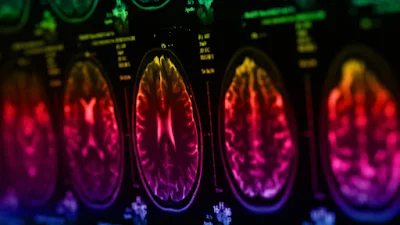

Richard Scolyer, de 57 años, fue diagnosticado en junio del año pasado con glioblastoma, un tipo de tumor cerebral agresivo y de rápido crecimiento. "El tiempo medio de supervivencia del glioblastoma es de 12 a 18 meses; sólo el 25 % de los pacientes sobrevive más de un año y sólo el 5 % sobrevive más de cinco años", explica The Brain Tumor Charity, una organización benéfica dedicada a financiar investigaciones sobre tumores cerebrales.

En la última actualización de su tratamiento, publicada en su cuenta de X el pasado 13 de mayo, afirmó: "¡No podría estar más feliz!". "El jueves pasado me hicieron una resonancia magnética cerebral en busca de glioblastoma recurrente (y/o complicaciones del tratamiento). Ayer descubrí que todavía no hay signos de recurrencia", escribió el especialista, adjuntando fotografías del proceso.